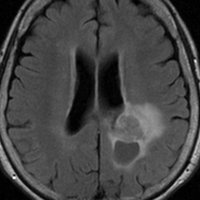

神経線維腫症1型に合併した退形成を示す anaplastic PXA

もともと停止性水頭症があり経過観察を受けていたNF-1の患者さんに発生したものです。嘔気と左片麻痺で発症しました。 開頭手術で亜全摘出(ほぼ全摘)しました。

術後に小さな腫瘍が残っていた(左の画像)ので54Gy/27frの放射線治療をしましたが,無効でした。結局,再開頭手術で残存腫瘍を摘出しました。3年後に同じ部位で再発(中央の画像)したので,また開頭手術で摘出しました。そのまた3年後に同じ部位で再発しました(右側の画像)。この様に,摘出しきれなければ治らないし,摘出できれば治る可能性の高い腫瘍です。腫瘍床での再発は多いものの,転移とか脳深部への浸潤性増殖は少ないといえる腫瘍です。放射線治療が効きにくいということを併せて,atypical meningioma WHO grade 2と似た性格を有しています。